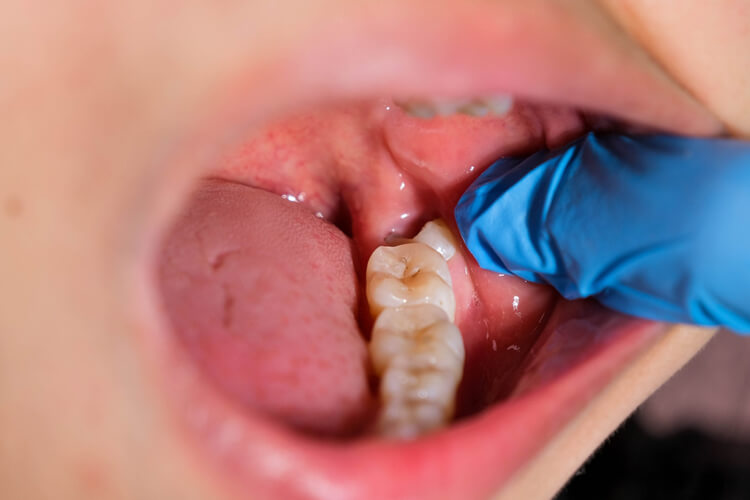

Surgery

Dental surgery involves various procedures to address complex oral health issues. These include tooth extractions, wisdom tooth removal, gum surgery, or corrective jaw surgery. Our skilled dental surgeons use advanced techniques to ensure comfort, minimize recovery time, and achieve the best possible outcomes.

Simple Extraction

Simple extraction is a straightforward dental procedure used to remove a tooth that is damaged, decayed, or causing discomfort. The tooth is loosened with special instruments and then carefully removed without the need for surgical incision. This procedure is typically quick, minimally invasive, and performed under local anesthesia to ensure patient comfort.

Surgical Extractions

Surgical extraction is a more complex dental procedure used to remove teeth that are impacted, broken, or not easily accessible through a simple extraction. This may include wisdom teeth or teeth that are deeply embedded in the gums or bone. The procedure involves making an incision in the gum tissue to access the tooth, and in some cases, removing part of the bone surrounding the tooth.

Wisdom Tooth Extraction

Wisdom tooth extraction is a common surgical procedure to remove one or more of the third molars (wisdom teeth), typically located at the back of the mouth. These teeth often cause issues such as pain, infection, or crowding due to their late eruption.

Impacted Extraction

Impacted tooth extraction is a dental procedure used to remove a tooth that is unable to fully emerge through the gum due to obstruction or misalignment. The procedure involves making an incision in the gum to access the impacted tooth, and may require removing a portion of the bone or breaking the tooth into smaller pieces for easier removal.